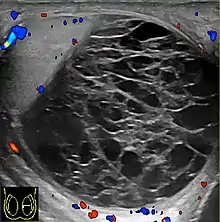

![]() Sonography of a normal testis. The normal testis presents as a structure having homogeneous, medium level, granular echotexture. The mediastinum testis appears as the

hyperechoic region located at the periphery of the testis as seen in this figure. | |

The normal adult testis is an ovoid structure measuring 3 cm in anterior-posterior dimension, 2–4 cm in width, and 3–5 cm in length. The weight of each testis normally ranges from 12.5 to 19 g. Both the sizes and weights of the testes normally decrease with age. At ultrasound, the normal testis has a homogeneous, medium-level, granular echotexture. The testicle is surrounded by a dense white fibrous capsule, the tunica albuginea, which is often not visualized in the absence of intrascrotal fluid. However, the tunica is often seen as an echogenic structure where it invaginates into the testis to form the mediastinum testis. In the testis, the seminiferous tubules converge to form the rete testes, which is located in the mediastinum testis. The rete testis connects to the epididymal head via the efferent ductules. The epididymis is located posterolateral to the testis and measures 6–7 cm in length. At sonography, the epididymis is normally iso- or slightly hyperechoic to the normal testis and its echo texture may be coarser. The head is the largest and most easily identified portion of the epididymis. It is located superolateral to the upper pole of the testicle and is often seen on paramedian views of the testis. The normal epididymal body and tail are smaller and more variable in position.